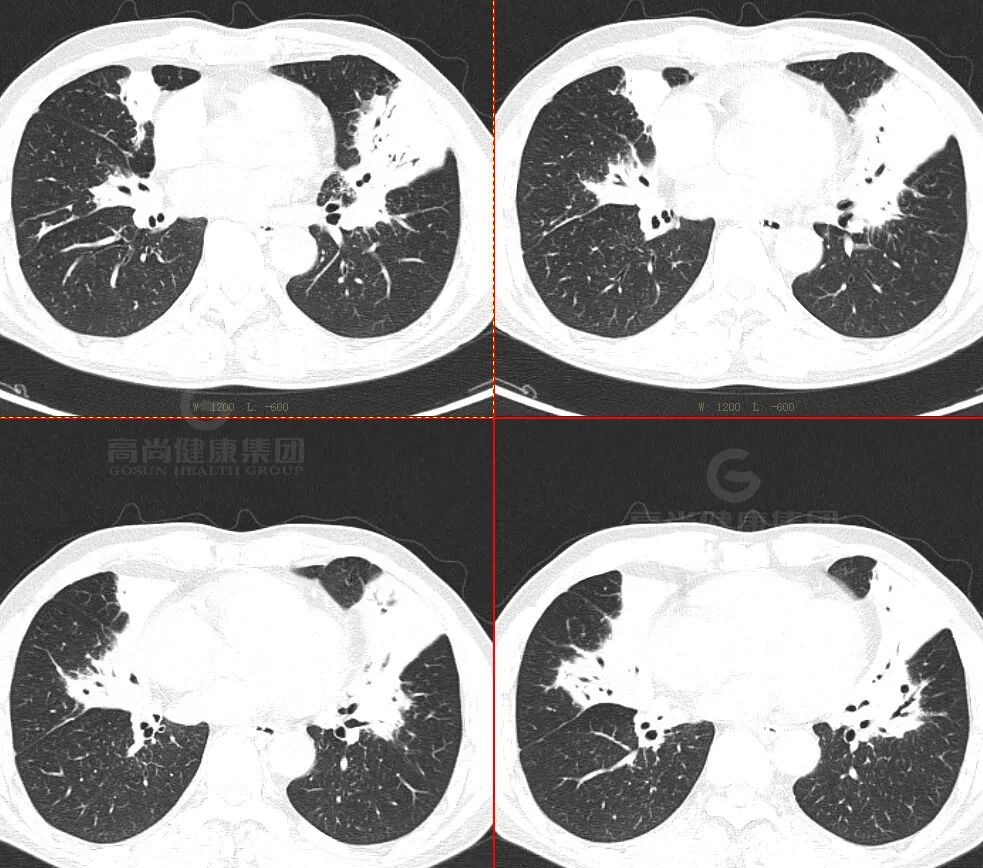

· 双肺多发结节、肿块,周围晕征

· 以胸膜下分布为主

· 强化较明显,未见空洞、钙化,坏死不明显

· FDG 代谢增高,SUVmax 为 18.3

影像学表现——晕征样结节和楔形实变影

早期出现多发密度增高的结节影,周围可见晕征。「晕征」表现为围绕结节周围的略低于结节密度而又高于肺实质密度的环行带状区,其病理基础是肺曲菌破坏肺部小血管,导致肺实质出血性坏死。「晕征」是 IPA 早期最具提示性的特征性 CT 表现,也是活性曲霉菌存在的标志, 见于 40~69% 的早期病例,高峰期为病变的第 5 天(1-30 天)。

「楔形实变影「:表现为以胸膜面为基底节段性实变影,边缘模糊,与栓塞性肺梗死相似,病理基础为出血性肺梗死。

晕征:凝固坏死+病变周围出血